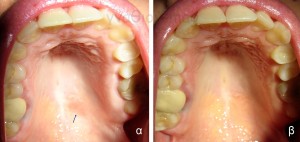

Όπως συμβαίνει στο δέρμα, υπάρχουν και στο στόμα βλάβες από ερεθισμό, οι οποίες δεν έχουν πάντοτε ανάγκη θεραπευτικής παρέμβασης (Εικόνα 1).